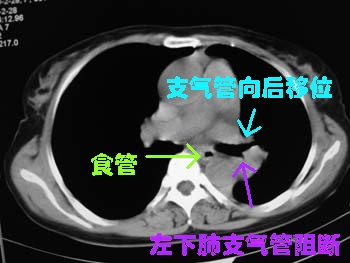

左侧胸廓容积缩小,纵隔左移,左下肺支气管闭塞.考虑中心型肺癌并左肺下叶不张,建议纤支镜.

属典型的左下肺中央型肺癌——左下分叶状肺肿块、支气管阻断、左下肺不张,纵隔淋巴结肿大。

左侧肺部体积缩小,纵隔向患侧偏移,左下肺支气管阻塞,中央型肺癌合并肺不张可能性大。

左下叶支气管变窄消失,考虑左侧中心型肺癌伴纵隔淋巴结增大

左下肺团块状软组织密度影,呈分叶状,边界清,未见小毛刺,左下肺支气管阻塞,纵隔见肿大淋巴结,考虑左下肺中央型肺癌伴纵隔淋巴结肿大,建议支纤镜检查。